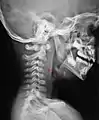

L'espace rétropharyngien est un espace anatomique médian situé entre la paroi postérieure du pharynx et la colonne vertébrale recouverte des muscles prévertébraux et de la lame prévertébrale du fascia cervical.

L'espace rétropharyngien est limité en haut par la partie basilaire de l'os occipital et se prolonge à sa base par le médiastin à partir de la fourchette sternale.

Latéralement, il est limité par la lame sagittale qui le sépare de l'espace latéro-pharyngien et de la gaine carotidienne.